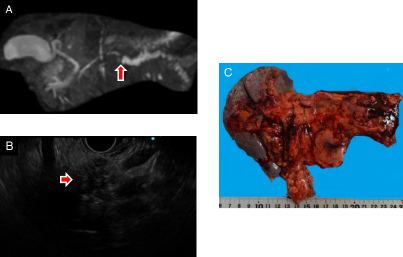

膵体尾部切除と術後化学療法を行った膵癌症例

膵体部に主膵管の閉塞を伴う膵癌も認めました(矢印)。

リンパ節郭清を伴う膵体尾部切除と術後化学療法を行い、約2年間無再発生存中です。

A.MRIによる膵管造影、B.内視鏡エコーによる膵腫瘍像、C.切除標本